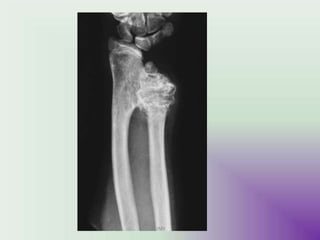

Osteochondroma. On this lateral view of the ankle, a

benign osteochondroma is seen projecting posteriorly

on a stalk. The end (arrows) is often covered with a

cartilaginous cap. These lesions always occur near a

UM

jo

Yint but point away from it.

Osteochondroma • Clinically, osteochondromas present asslow-growing masses, which can be painful if they impinge on a nerve or if the stalk is fractured. In many cases, they are detected as an incidental finding. Osteochondroma. On this lateral view of the ankle, a benign osteochondroma is seen projecting posteriorly on a stalk. The end (arrows) is often covered with a cartilaginous cap. These lesions always occur near a UM jo Yint but point away from it.